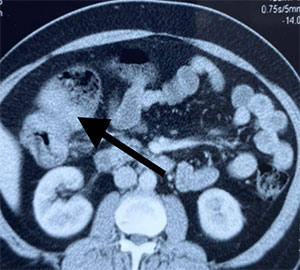

68 year old gentleman with history of abdominal pain, constipation & bloating was diagnosed with a tumor of right side of colon during investigations. The colonoscopic biopsy confirmed a colonic cancer. Incidentally the patient had suffered from a heart ailment (myocardial infarction- heart attack) 3 months back and underwent an angioplasty with stent placement with cardiology team. Unfortunately the anemia which was present then went untreated.

When the patient was refereed to us with the diagnosis of colonic cancer, the anemia was also looked at carefully. It was iron deficiency anemia due to blood lost in the stool from colon cancer. The anemia had probably precipitated the heart attack considering the fact that patient did not have diabetes, hypertension or dyslipidemia. Now the patient was in need of an early surgery due to impending intestinal obstruction from the lumen occluding colonic tumor but was on two blood thinners (medicines used to prevent platelets from coming together to avoid stent blockade). Operating patient on blood thinners makes surgery (especially a supramajor GI surgery) a very difficult proposition considering the fact that surgeon wants to at least stop one blood thinner medication to reduce perioperative bleeding complications, but this increases the risk of cardiac complications. Also the anemia needed attention preferably avoiding blood transfusion. Blood transfusions have shown to increase risk of tumor metastasis.

colonic cancer

colonic tumor

The treatment was started with intravenous iron therapy to replenish rapidly the iron stores in the body and thus boosting the hemoglobin levels. At an appropriate time prior to surgery stronger blood thinner was withheld and patient was subjected to surgery. A radical excision of right colon along with its draining lymph nodes was done (CME – Complete mesocolic excision). Small intestine was joined to the distal colon to establish intestinal continuity. The patient did exceedingly well and was discharged on 7th postoperative day without any complications. The surgery was done without any blood transfusion. Patient has been advised to undergo chemotherapy based on the final histopathological staging of the tumor.